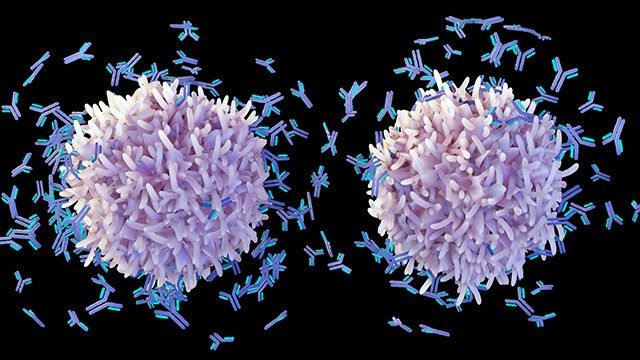

Blinatumomab, a bispecific T-cell engager, is an effective treatment for patients with relapsed or refractory B-cell acute lymphoblastic leukemia (B-ALL) when administered as a continuous intravenous infusion over four weeks. However, this drug administration method can be burdensome to patients.

4. Targeted combination with evorpacept for patients with B cell non-Hodgkin lymphoma

Paolo Strati, M.D., associate professor of Lymphoma and Myeloma, had led a Phase I study of evorpacept (a novel high-affinity signal regulatory protein that blocks CD47), with lenalidomide and rituximab (R2) in patients with relapsed or refractory indolent B cell non-Hodgkin lymphoma. The combination was safe, and more than 80% of patients had a complete response.

Strati is now presenting a Phase II study investigating the efficacy of this regimen in patients with previously untreated indolent B cell non-Hodgkin lymphoma and a high tumor burden. These included patients with both follicular lymphoma and marginal zone lymphoma.

The results indicated that adding evorpacept to R2 is safe and effective as a frontline non-chemotherapy treatment for indolent B cell non-Hodgkin lymphoma. In the study, 92% of patients experienced a complete response, and 8% had a partial response, for an overall response rate of 100%. With limited follow-up, responses seem durable. The researchers are currently evaluating serial blood samples for circulating tumor DNA to determine the minimal residual disease eradication rate with this novel regimen.